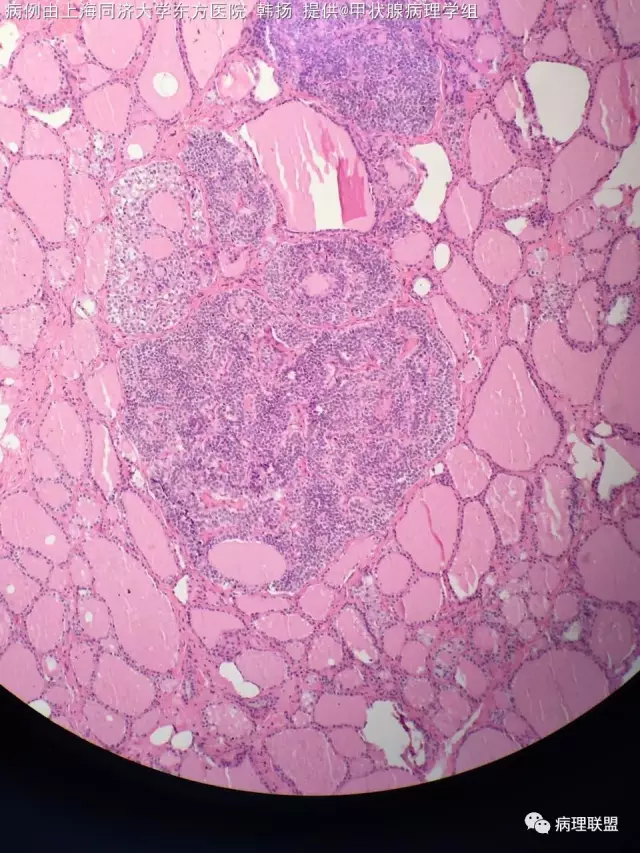

男54岁,右甲状腺是乳头状癌,滤泡亚型,左侧也发现直径0.4cm结节,边界不清。以下图片是左叶结节。(病例由上海同济大学东方医院 韩扬 提供,致谢!)